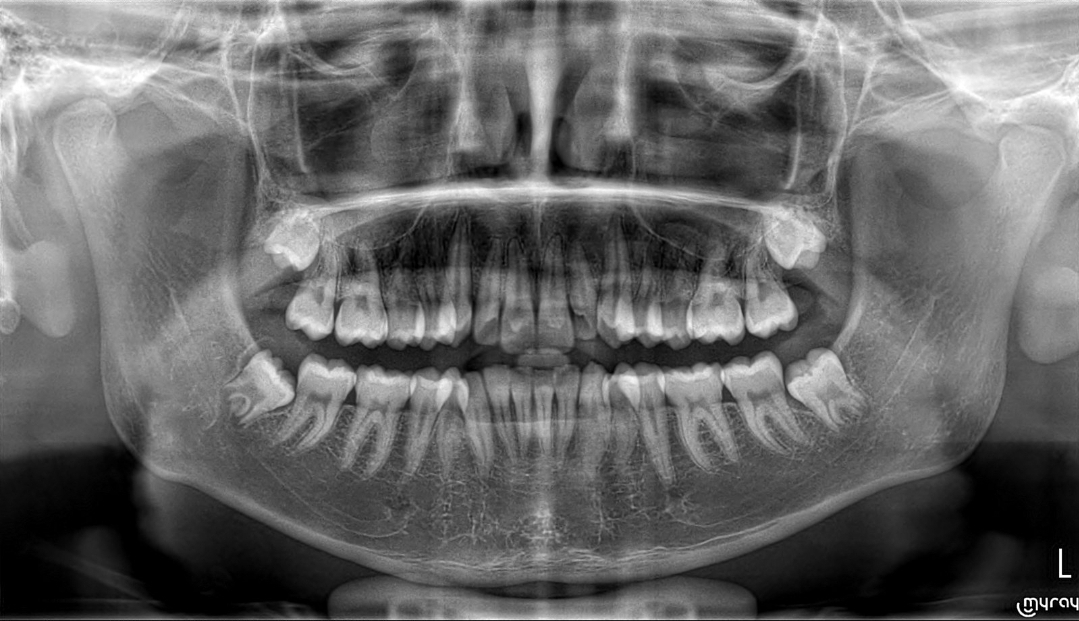

I heard it can flatten your maxilla. Im already having them so just wanna hear ur opinion

i got wisdom teeth extractionUnless you get extractions or your ortho plans to push the teeth back youre fine bro

Dont get them, they will recess your madible and maybe flatten the maxillai got wisdom teeth extraction

Dont get them, they will recess your madible and maybe flatten the maxilla